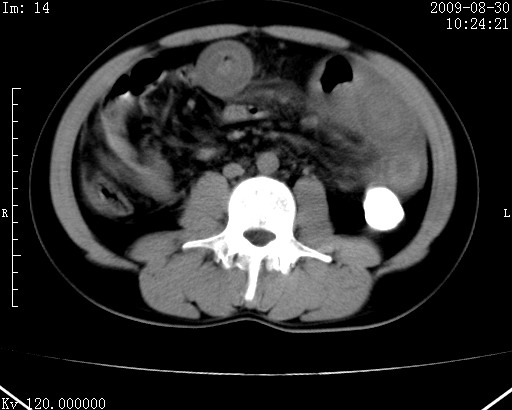

患者唐某,男31岁,已婚,本地务农。

自述入院前两天一次进食较多冷饮之后,出现阵发性上腹部疼痛,次日加剧伴恶心、呕吐,呕吐后症状稍减轻。食欲差。大便每天1-2次,量少,暗红色水样。小便赤。无畏寒、发热、咳嗽等呼吸道症状。无高血压及胃病史。

检查:体温、血压及脉搏正常.皮肤无黄染,浅表无淋巴结肿大。左腹肌紧张,左上腹有压痛,无反跳痛,可触及包块。

生化:钾、钠、氯、钙、ph正常,总胆红素和直接胆红素稍高,空腹血糖稍高。

尿淀粉酶:1256 u/l(正常60-401)。

血常规:wbc 22.4x109/l gr88% ly9.6%其余基本正常。

胃镜:急性胃炎。立位腹平片:未见异常。

下面是ct平扫,降结肠内是对比剂。

术前影像诊断:上段空肠急性缺血性坏死并腹水。建议手术治疗。

术中见上段空肠约70cm长范围坏死,从屈氏韧带远端约10cm处开始。坏死肠管肿胀变形变色,管壁明显环形增厚,部分聚成大肿块,无扭转和套叠。肠系膜上动脉分支内广泛泥沙状血栓。肠切除。

临床诊断:肠系膜上动脉梗塞并急性肠坏死。

开始时我们科也有人认为是套叠,最后统一意见,不考虑肠套。我们看到的“靶征”,“晕圈征”,“双圈征”实际上只是单根肠管的横断面。坏死肿胀后肠壁各层的密度不一样。

左侧腹小肠腔管壁明显增厚,部分内示靶征,走行异常,部分肠系膜绳样改变,肝包膜下及肠间较多液体密度,然梗阻近端肠腔积气不明显。

考虑;肠扭曲伴肠坏死。